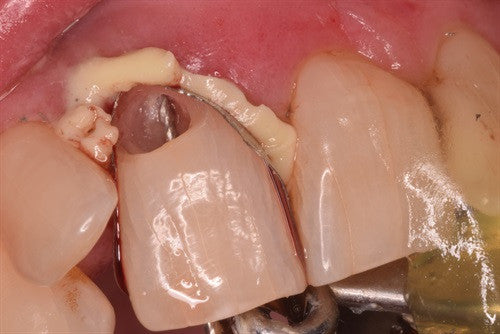

Direct Pulp Cap by Dr. Ahmad Fayad

Posted on May 15 2019

Noteworthy use of the Greater Curve technique by Dr. Ahmad Fayad. Introduction: 28 year old female with senstive Upper left first molar #26. No spontaneous pain, no lingering pain, no... Read More